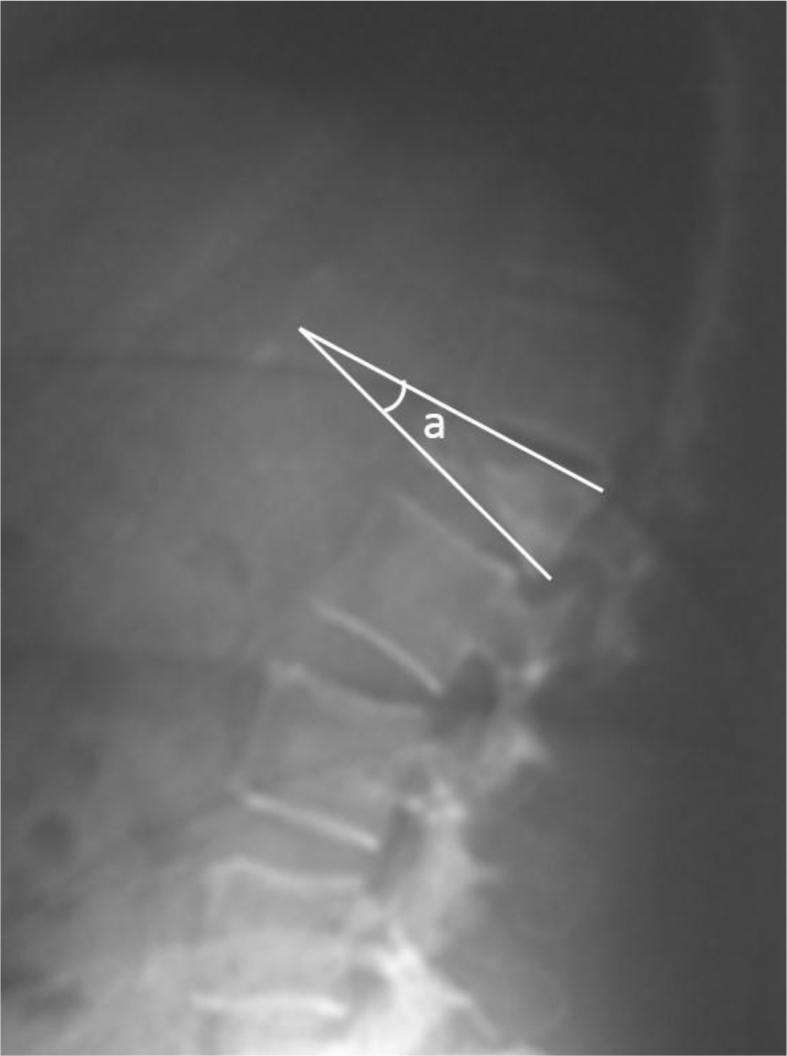

The files of the patients who underwent vertebroplasty or kyphoplasty for osteoporotic vertebrae fractures were retrieved from the archives. Forty-three patients with complete follow-up data were included in the study group. The patients were evaluated for radiological outcomes in terms of local kyphosis angle, wedging index, compression ratio, visual analog pain scale (VAS) and Oswestry Disability Index (ODI).

从档案中检索接受椎体成形术或后凸成形术治疗骨质疏松性椎体骨折患者的病历。研究组纳入了43例有完整随访数据的患者。对患者进行局部后凸角、楔形变指数、压缩率、视觉模拟疼痛量表(VAS)和Oswestry功能障碍指数(ODI)等影像学结果评估。

研究组中,22例患者(17例女性,5例男性;平均年龄:73岁)的24个椎体接受了后凸成形术,而21例患者(16例女性,5例男性;平均年龄:74.7岁)的24个椎体接受了椎体成形术。平均随访时间为26个月。分析两组的VAS和ODI值时,两组术后均显示出统计学上的显著进步。影像学数据显示,后凸成形术组矢状面指数值有统计学上的显著改善,而椎体成形术组则没有。总体并发症发生率为4%。